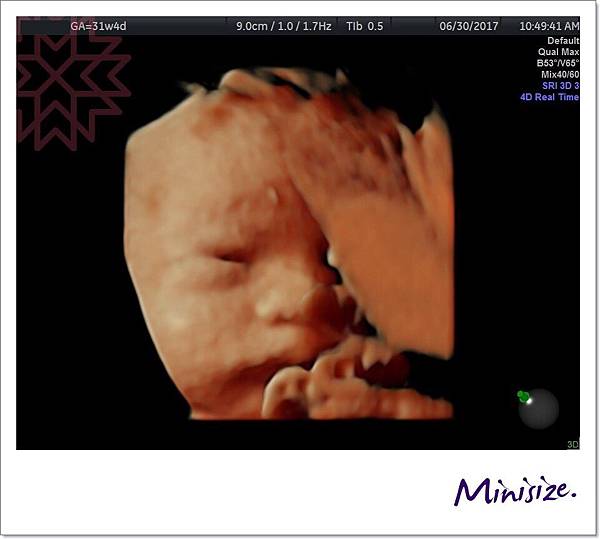

31週時

第一次看到Timo睜開雙眼

經驗豐富的醫生也驚嚇地說她很少看到寶寶眼睛張這麼大

後來 Timo又躲起來

醫生搖肚皮搖好久後

正當麻麻跟醫生、護士聊天

說到寶寶好像都知道產檢的時候會被超音波偷拍

不想要自己的隱私被打擾!

麻麻還說是偶像包袱嗎?

Timo立馬用「偷瞪」的表情回應我們

哈哈哈哈哈

這怪表情把我們都逗樂了~

最後

Timo秀出愛睏想睡覺的表情

我們就不打擾他了